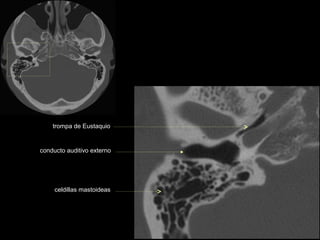

seno maxilar

conducto

carotídeo

auditivo externo

protuberancia

occipital externa

trompa de Eustaquio

conducto auditivo externo

celdillas mastoideas